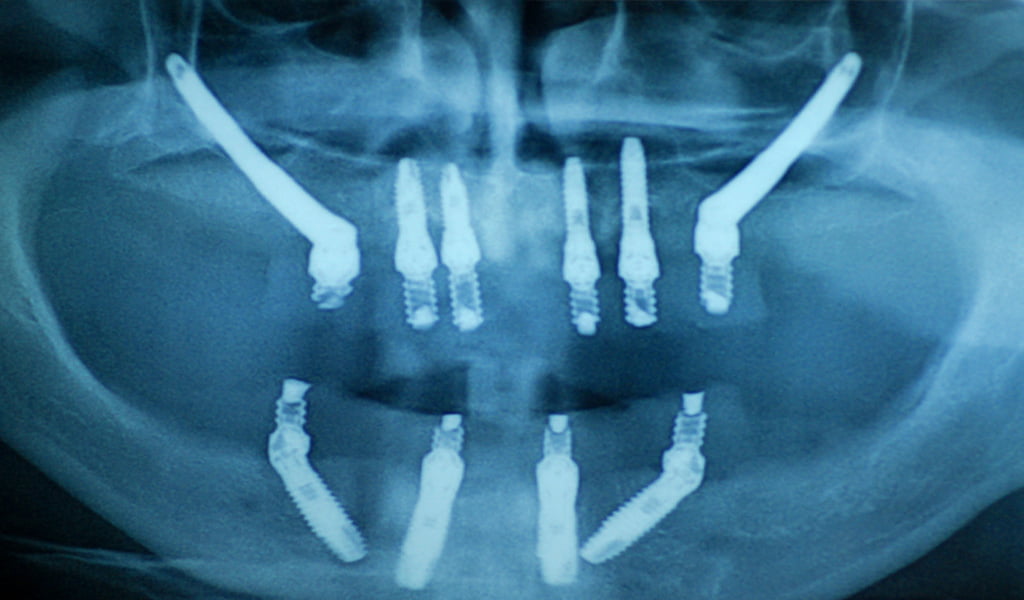

1. Implants zigomàtics

Es basa en un concepte innovador que permet oferir un gran nombre d’avantatges als pacients amb poc os. És una tècnica avançada que consisteix a col·locar uns implants llargs en l’os zigomàtic (àrea del pòmul) per a eliminar la necessitat d’empelts ossis.

El mateix dia de la intervenció, es col·loca una pròtesi fixa sobre els implants, que ofereix òptimes prestacions estètiques i funcionals de manera immediata.

Els implants zigomàtics són una solució que aporta seguretat, confort i estètica. Així doncs, retornen als pacients una qualitat de vida de la qual feia anys que no gaudien i que creien no poder recuperar.